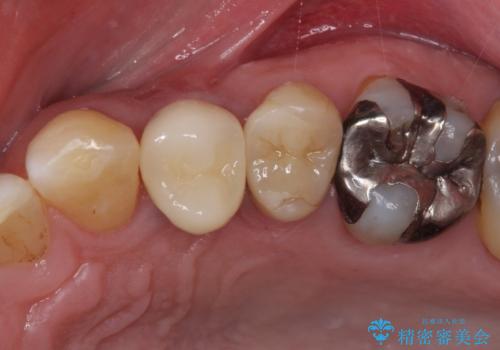

割れてしまった小臼歯 インプラントによる補綴治療

- 他院で抜歯が必要と診断され、再度診断を希望して来院された患者様です。

顕微鏡下で診察を行ったところ、歯根が垂直に破折していたため、抜糸してインプラントによる補綴治療を行うこととしました。

より審美的で、より機能的に優れた治療をご希望とのことであったので、ジルコニアカスタムアバットメントを用いたインプラント治療を行うこととしました。